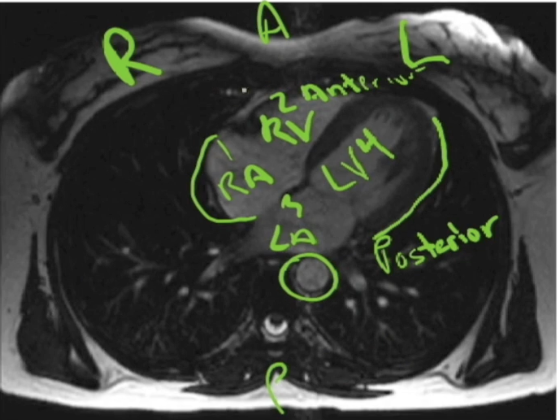

imaging

A